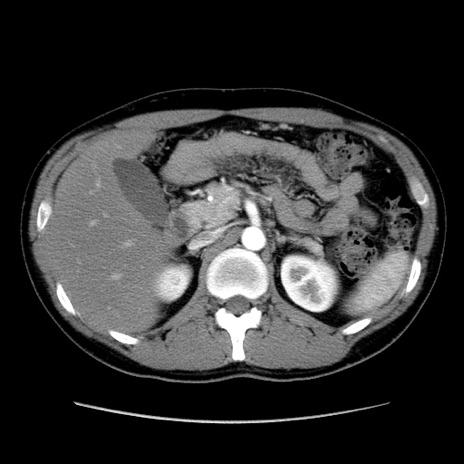

症例36(横断像)

【症例】20歳代 男性

【主訴】心窩部痛

【現病歴】今朝より上腹部痛あり。一旦軽快していたが再度出現したため救急要請。昨日夕に白身の魚を含む刺身を食べた。

【身体所見】BP 136/89mmHg、HR 74/min、BT 37.0℃、腹部:膨満、軟、心窩部に圧痛あり。反跳痛なし、筋性防御なし、腸雑音やや亢進あり。

【データ】WBC 17700、CRP 0.48